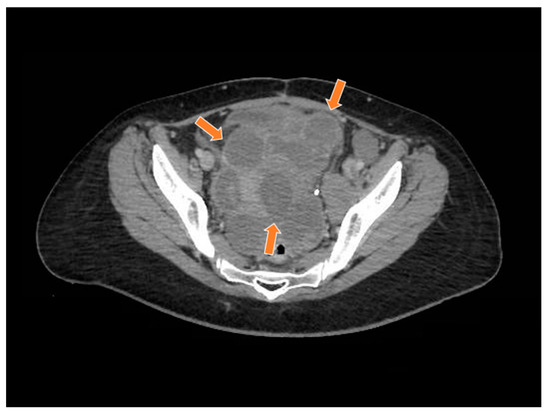

2. Case Report